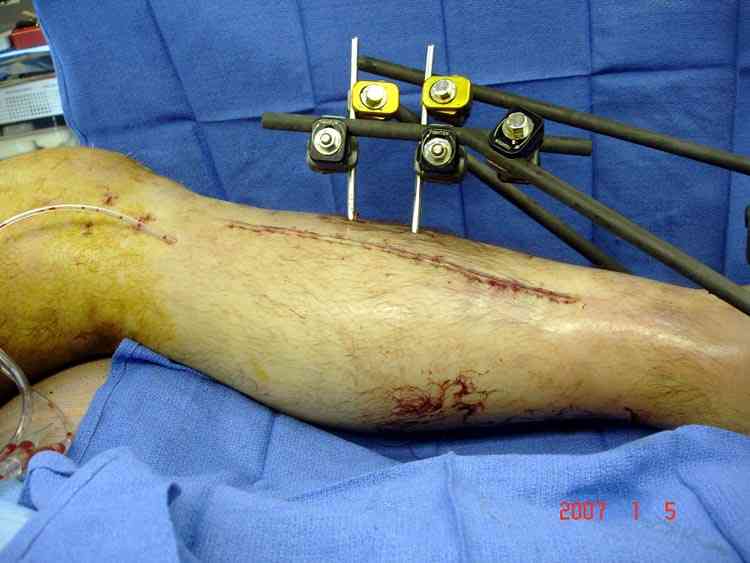

Отечность в зоне фиксации является противопоказанием к открытому методу. Для профилактики осложнений с фиксацией можно повременить применением стабилизирующего наружного фиксатора. Фиксатор восстанавливает длину конечности, облегчает в будущем репозицию и создает благоприятные условии для спадения отека. Также позволяет экономить средства, вместо дорогого стационара больной может находится на амбулаторном наблюдении. Появление симптома "skin wrinkle test" (морщинки) подскажет о готовности кожного покрова для окончательной операции на костях.

Множественная огнестрельная травма конечностей, перелом костей предплечья, фиксация в первые часы и дефект мягких тканей, мероприятия по закрытию...